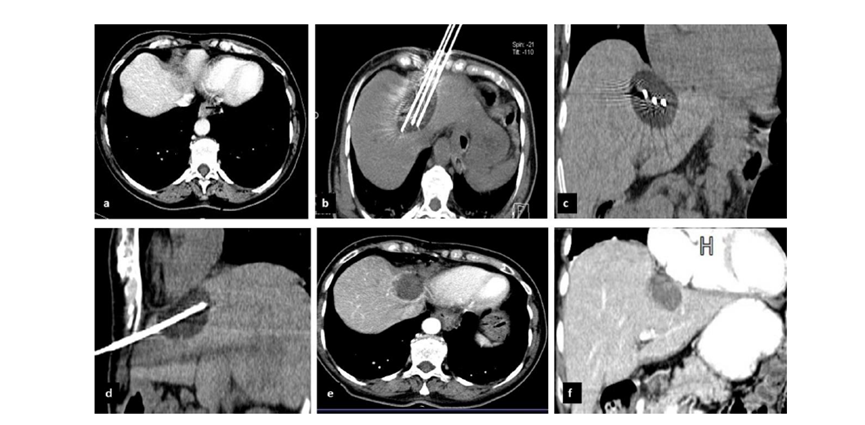

冷凍消融膽囊附近腫瘤病灶

(A)動脈期 MRI 顯示膽囊附近有外周增強病變(箭頭)。

(B)手術過程中 CT 顯示冷凍探針位于病灶內。

(C)消融后,術后 1 個月CT 顯示完全消融(箭頭)。

(A)動脈期CT圖像顯示有一個包膜下結節(箭頭)。(C) 在手術過程中的CT顯示一個冷凍探針位于病灶內。隨訪時間中位數為7個月(范圍:3-12個月),隨訪期間患者無局部腫瘤進展或死亡。

(A)門靜脈期 CT 圖像顯示膽囊附近有病變(箭頭)。(D)消融手術后 1 個月CT 顯示完全消融。